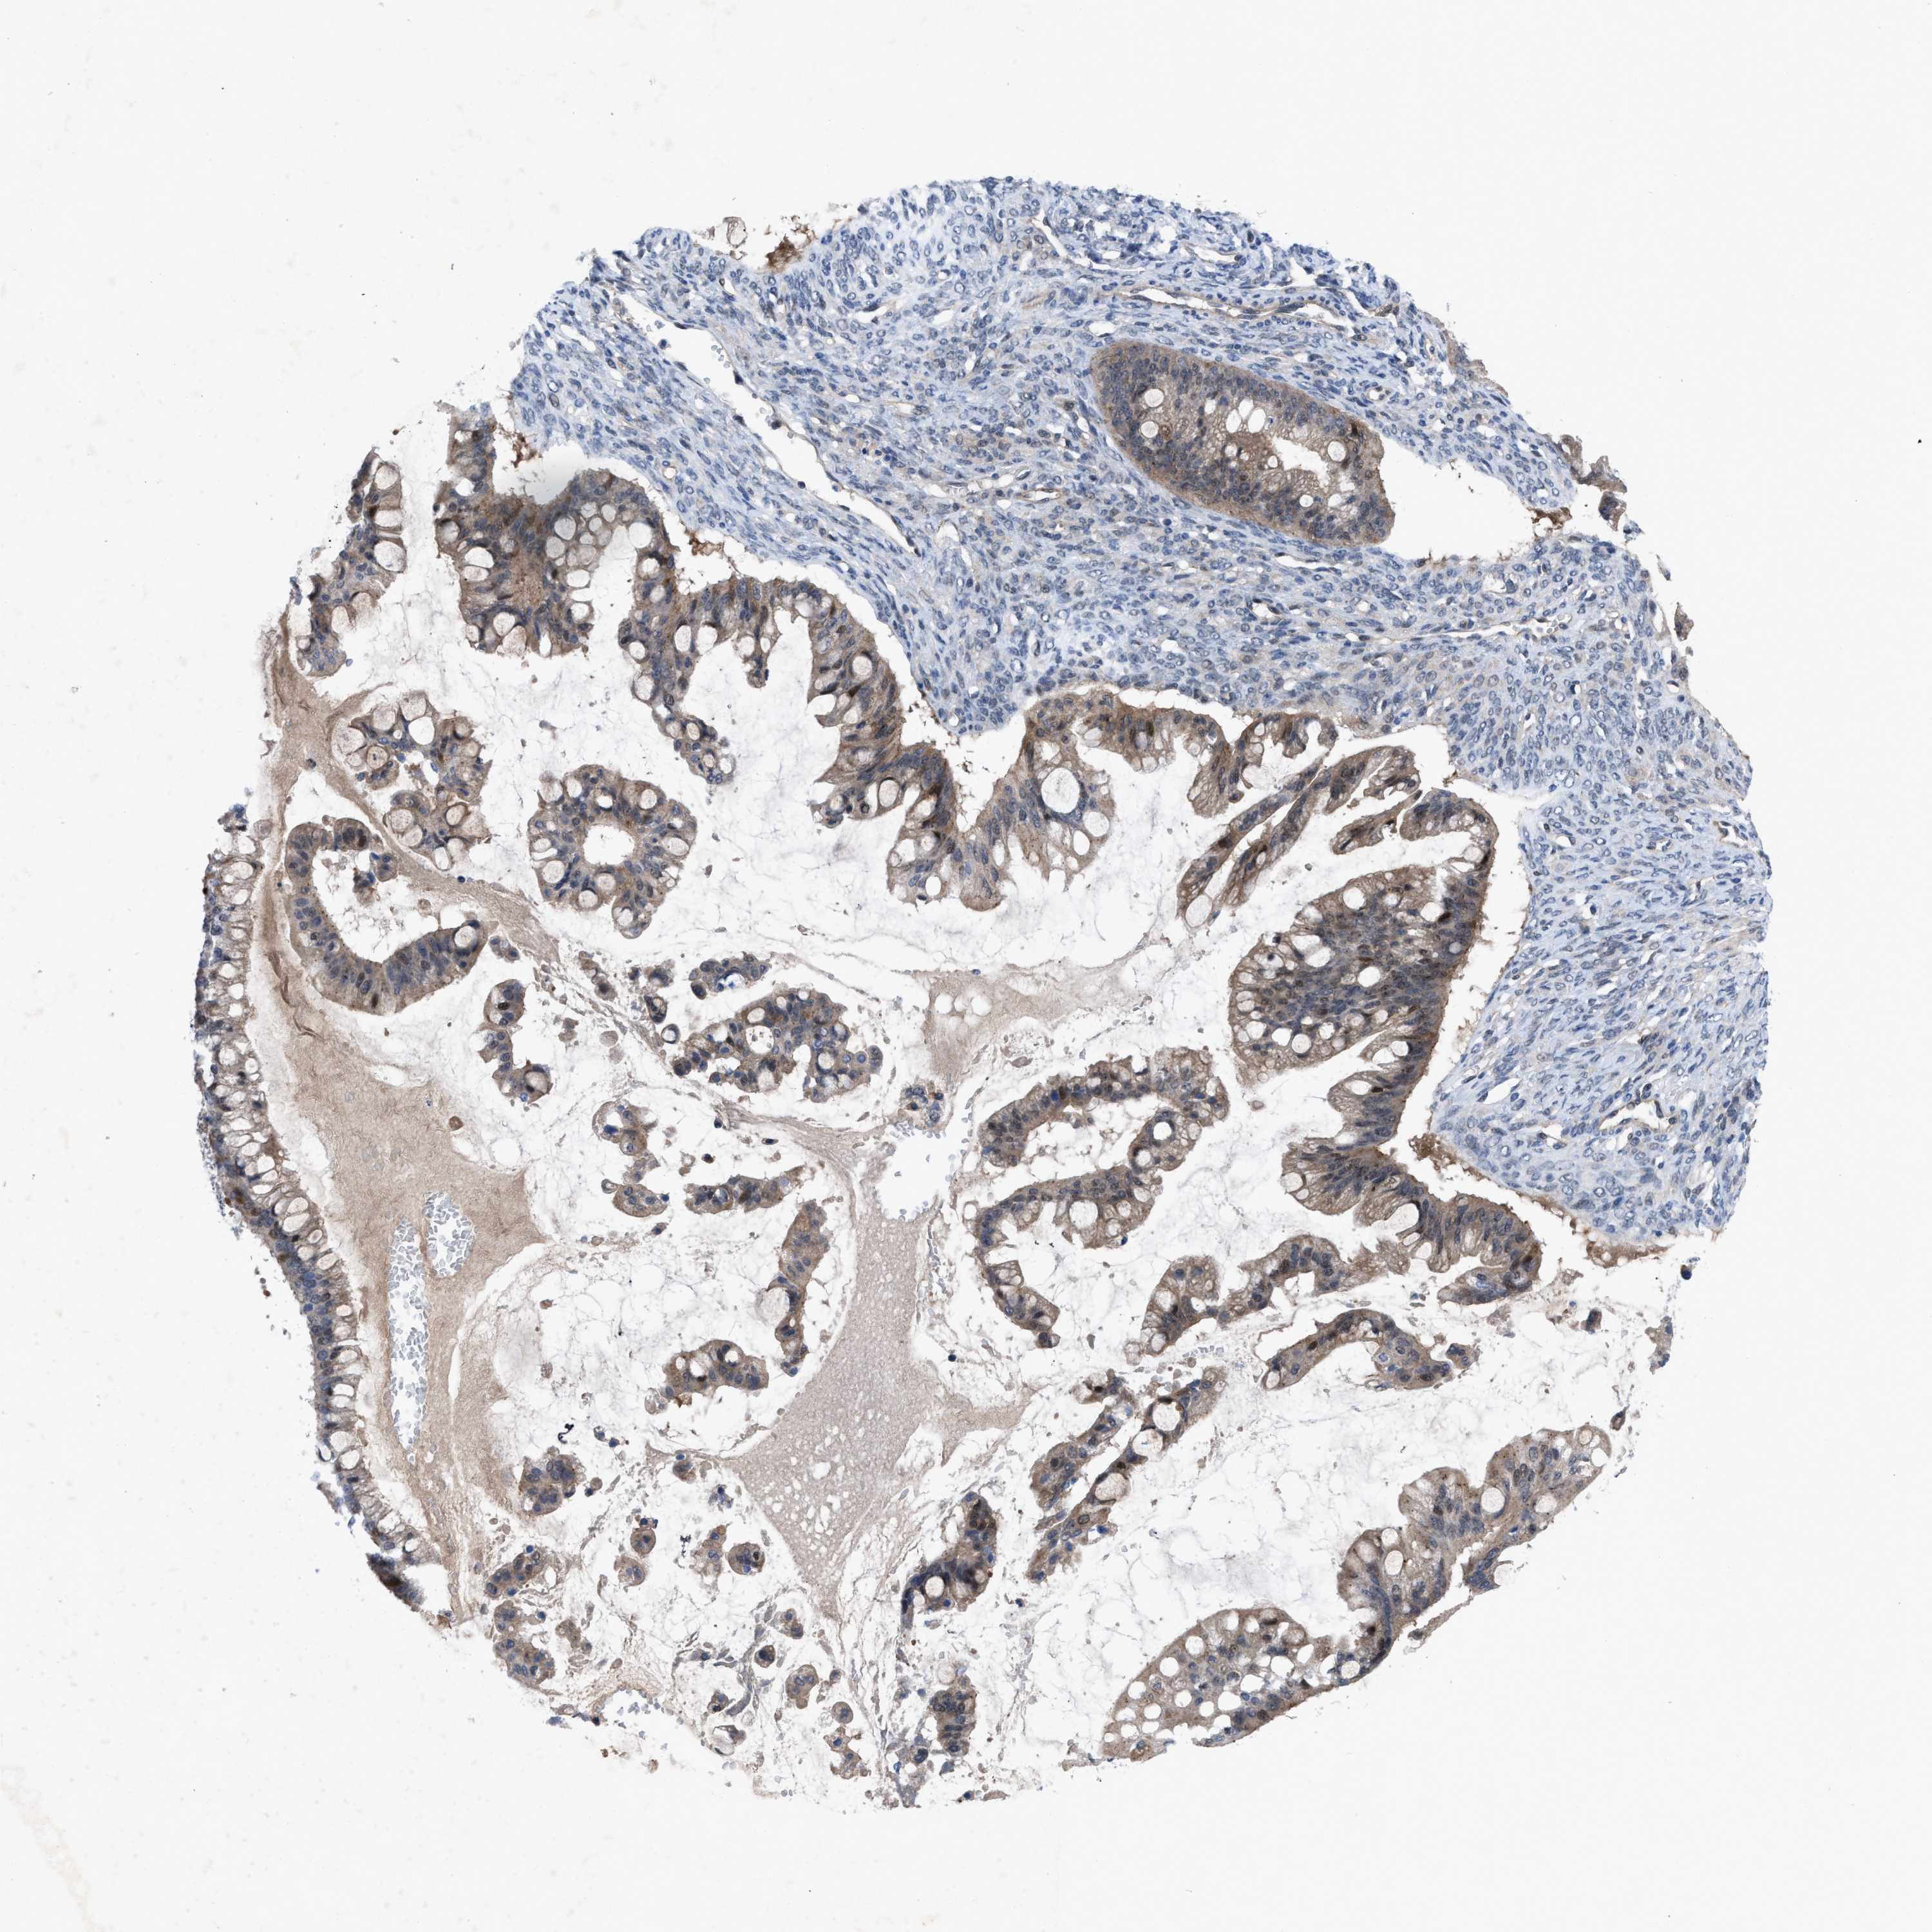

OVARIAN CANCER - Protein expressioni

A mouse-over function shows sample information and annotation data. Click on an image to view it in a full screen mode. Samples can be filtered based on level of antibody staining by selecting one or several of the following categories: high, medium, low and not detected. The assay and annotation is described here.

Note that samples used for immunohistochemistry by the Human Protein Atlas do not correspond to samples in the TCGA dataset.

Antibody stainingi

Antibody staining in the annotated cell types in the current human tissue is reported as not detected, low, medium, or high, based on conventional immunohistochemistry profiling in selected tissues. This score is based on the combination of the staining intensity and fraction of stained cells.

Each image is clickable and will lead to virtual microscopy that enables deeper exploration of all samples and also displays staining intensity scores, fraction scores and subcellular localization as well as patient and tissue information for each sample.

Antibody HPA019011

Staining

High

Medium

Low

Not detected

Intensity

Strong

Moderate

Weak

Negative

Quantity

>75%

75%-25%

<25%

None

Location

Nuclear

Cytoplasmic/membranous

Cytoplasmic/membranous,nuclear

Cystadenocarcinoma, serous, NOS

Carcinoma, endometroid

Cystadenocarcinoma, mucinous, NOS

Carcinoma, NOS